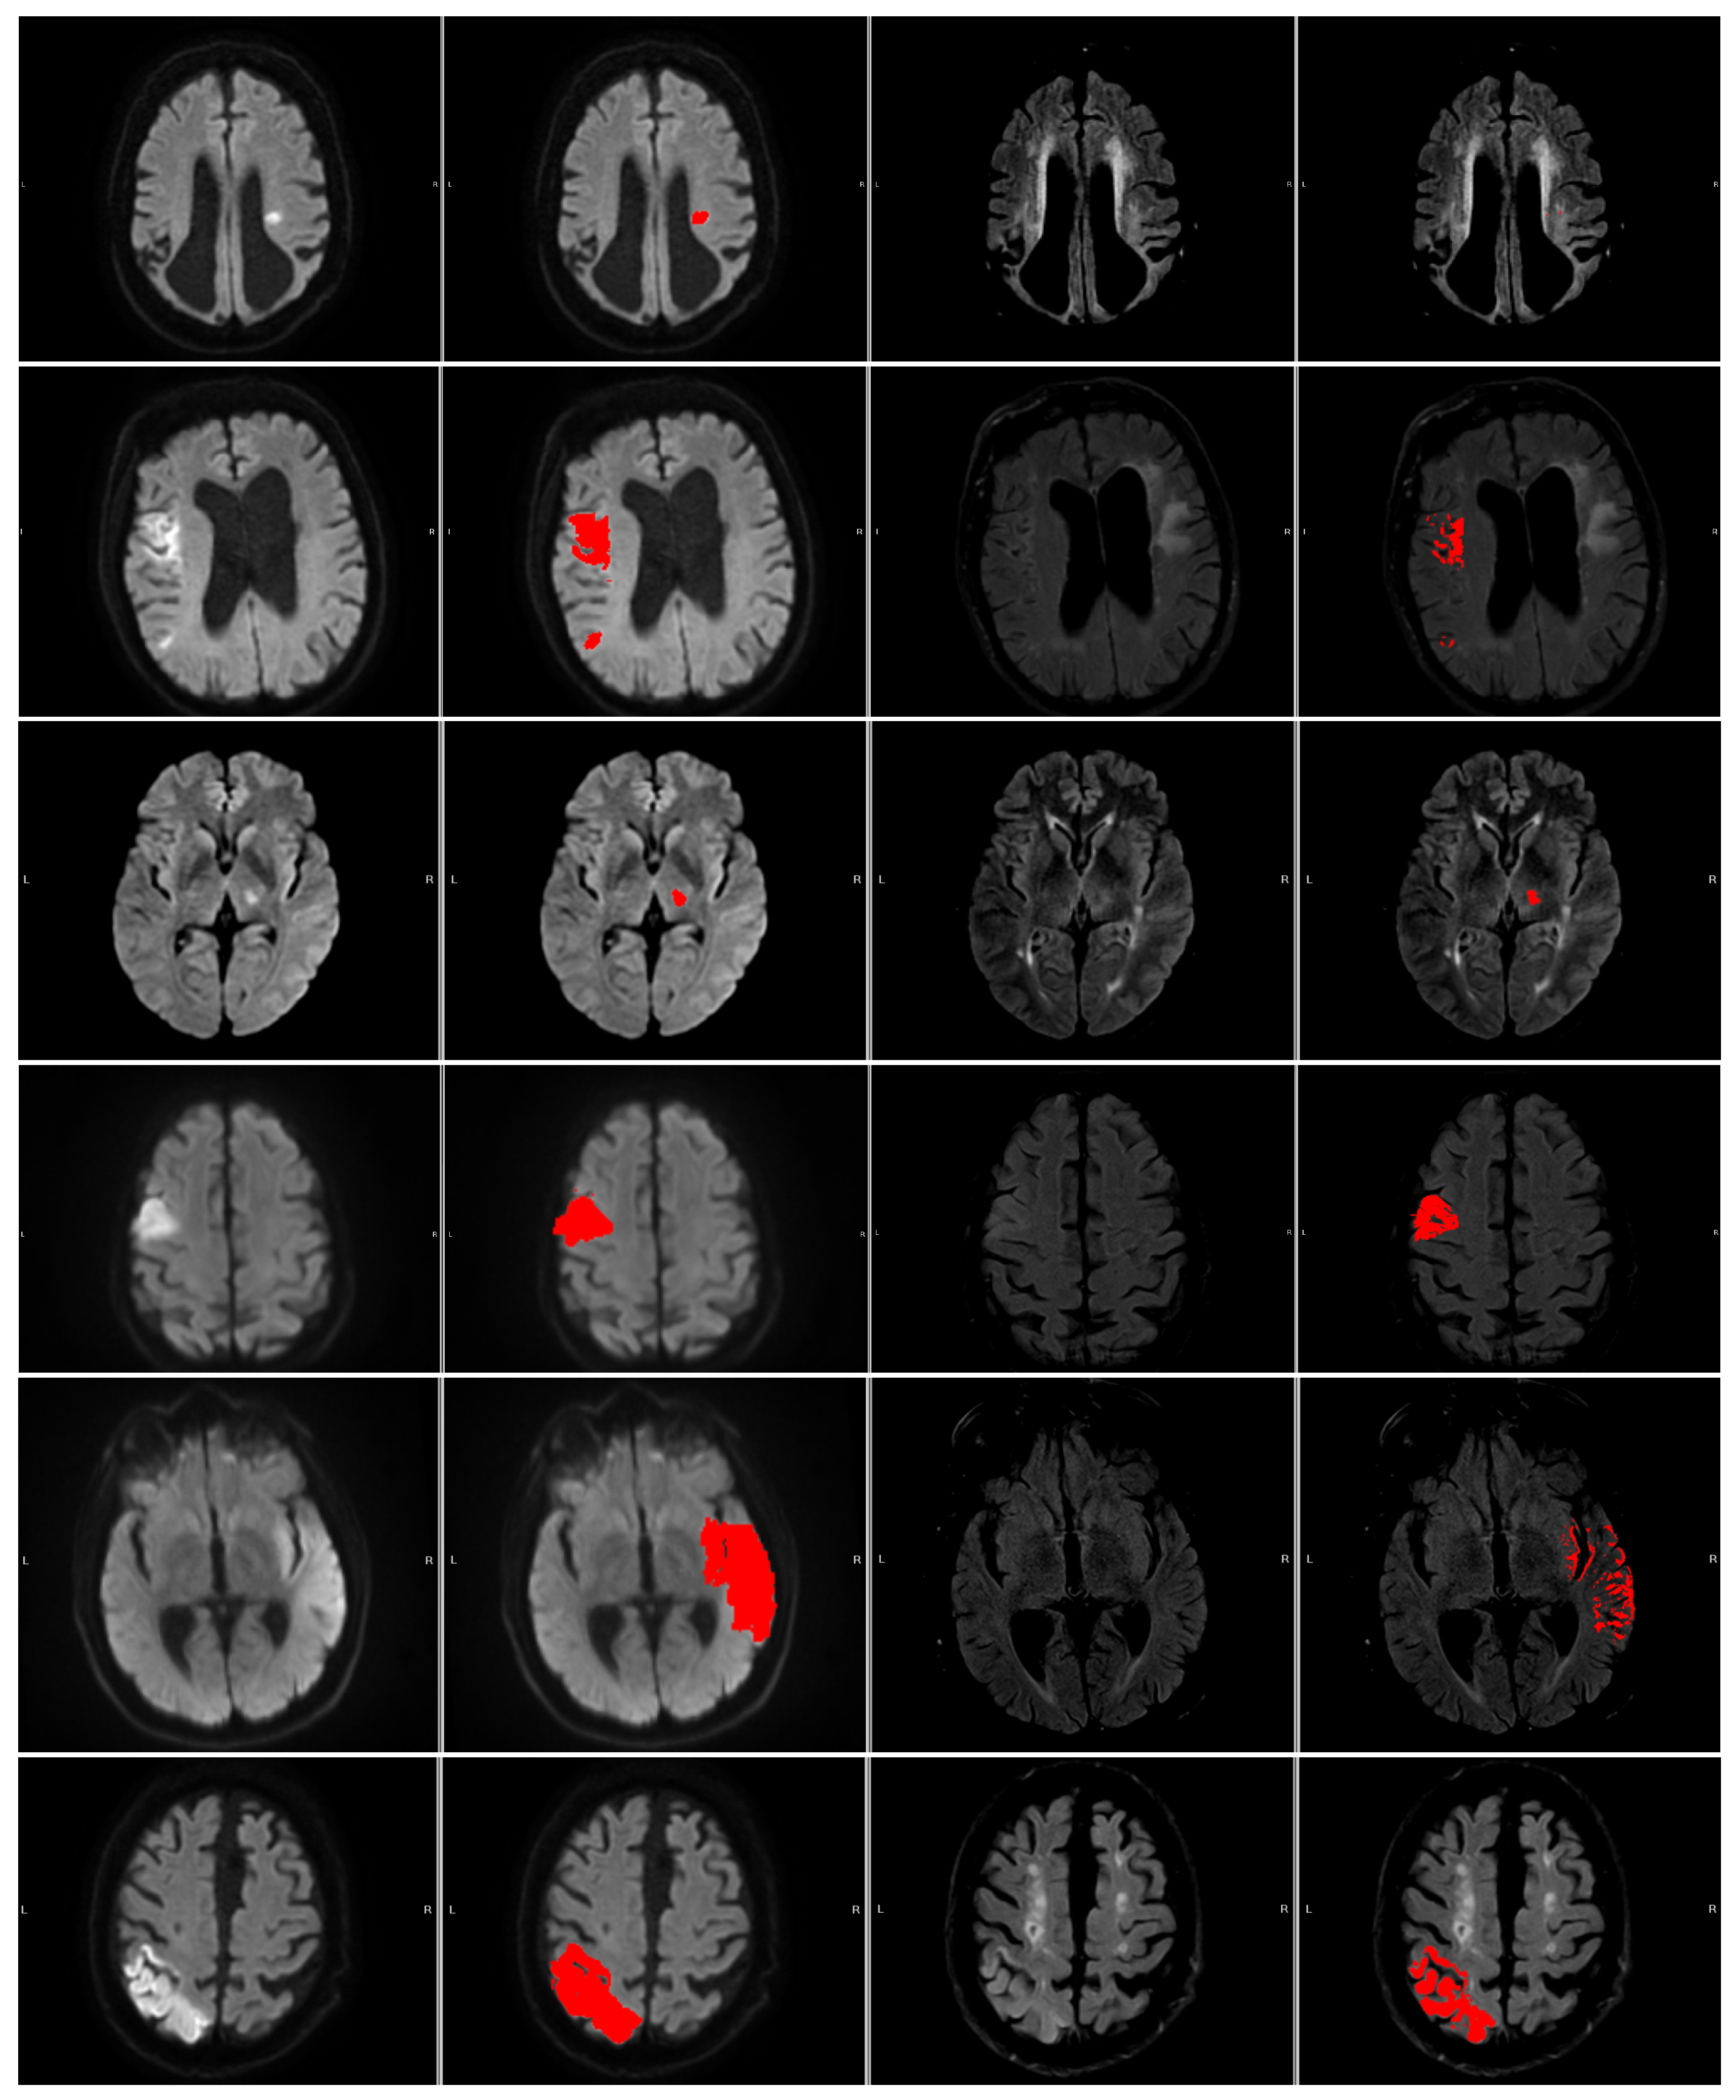

We correlated the clinical mismatch assessment obtained from electronic patient records with our two measures, the DWI/FLAIR mismatch ratio ranging from 0 (complete mismatch) to 1 (complete match) and the intensity ratio measure. A plot of these measures along with the mismatch assessment can be seen in Figure 4.

The 6 numerated cases can be seen in Figure 5. Case 1 is a situation where both the area of interest and the contralateral side are slightly hyperintensive, leading to a small DWI/FLAIR mismatch ratio but large intensity measure and a no-mismatch assessment in the clinic. In Case 2, part of the contralateral side is hyperintense, which may lead to slight under-segmentation. However, the contralateral hyperintensity is not large enough to be clear from the intensity measure. Cases 3 and 4 correspond to two cases where the patients are deemed to be mismatch cases at the hospital, but our measures disagree. Case 5 shows a mismatch assessed case where the measures agree. Case 6 shows a no-mismatch assessed case where the measures and the assessment agree. Furthermore, the case shows the relevance of our criterion that the intensity be brighter than the mean plus 0.25 standard deviations, as part of the contralateral side is hypo-intense.

Figure 5. The numbered outlier cases from Figure 4. The cases are presented in ascending order 1 (top) through 6 (bottom). All cases are shown as (left to right) DWI (b1000), DWI (b1000) with segmentation (red area), FLAIR, and FLAIR with segmentation (red area).